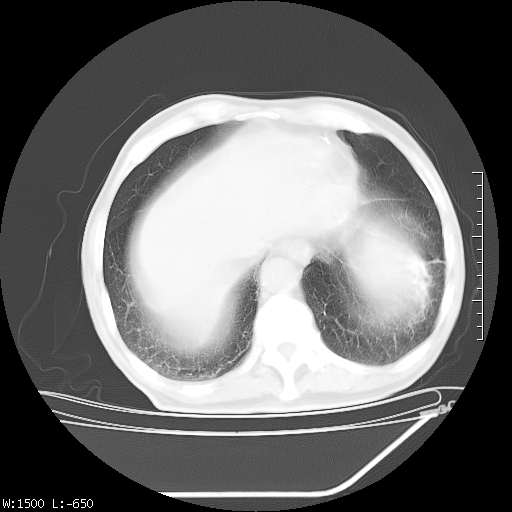

标题: CT23994:男、72、咳嗽、气短两月余,近来消瘦。 [打印本页]

标题: CT23994:男、72、咳嗽、气短两月余,近来消瘦。

tb可能性大(双肺均可见片状密度增高灶,其内可见低密度空洞)。

双肺继发性肺结核

右上肺大片状密度增高影,与胸膜关系密切,内见低密度透亮影,胸膜下可见三角形不张影,左下肺沿支气管走形结节影,纵膈内淋巴结显示。考虑结核并疤痕性不张可能性大,建议穿刺活检,排除肺泡癌。